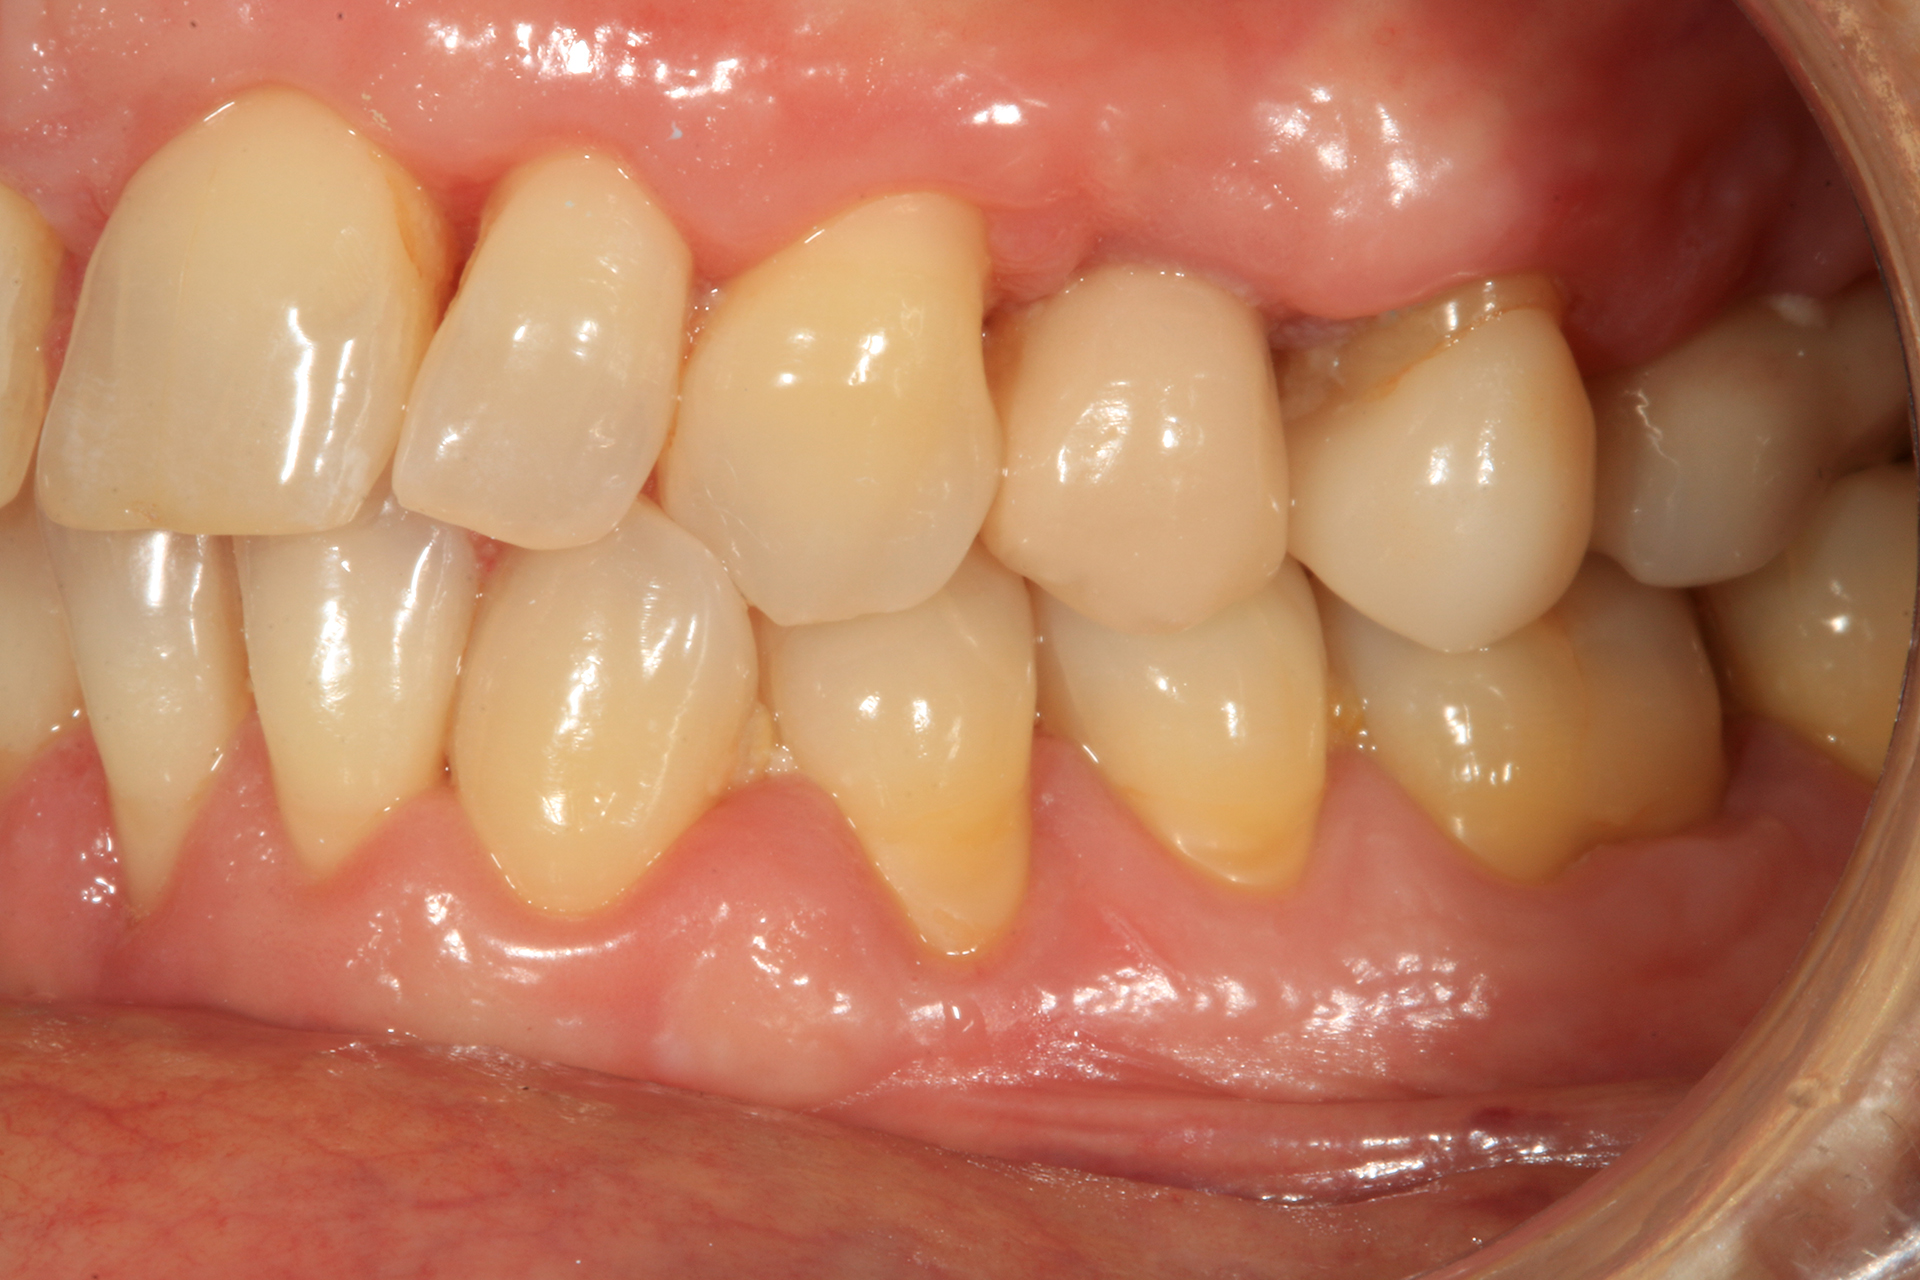

Il 20% degli impianti è stato posizionato nella mandibola (per lo più in posizione 47) e il restante 80% nel mascellare superiore (il 20% in posizione 16 e il 20% in posizione 25). Gli impianti posizionati nel mascellare superiore hanno trovato un osso tipo IV, mentre gli impianti posizionati nella mandibola hanno trovato un osso tipo III. Gli impianti utilizzati hanno un diametro compreso tra 4.0 e 4,5 mm (il 66.7% sono da 4.0 mm) e una lunghezza compresa tra 4.5 mm e 7.5 mm (il 53.3% sono lunghi 7.5 mm). Nell’86.7% dei casi non è stato eseguito alcun procedimento chirurgico aggiuntivo; in un caso, due impianti hanno previsto in rialzo di seno transcrestale con PRGF-Endoret e osso autologo. Nel 93.3% dei casi la protesizzazione ha previsto ponti avvitati a più elementi; un impianto è stato protesizzato mediante elemento singolo avvitato con componente transepiteliale. Il follow-up medio è stato di 12.4 ± 1.05 mesi dal carico. Il 100% degli impianti è sopravvissuto, senza complicanze né chirurgiche né protesiche. La perdita di osso media a 12 mesi è stata mesialmente di 0.15 ± 0.74 mm e distalmente di 0.13 ± 0.85 mm. La Figura 4 mostra l’osso perso su un singolo impianto e le Figure 5-14 illustrano un caso clinico rappresentativo.

Gli impianti Core-X® sono disegnati in modo da garantire una migliore stabilità primaria in osso a bassa densità o gravemente riassorbito, in siti post-estrattivi o zone con volume osseo residuo limitato. La piattaforma stretta e il corpo reso compatto dalla struttura della filettatura preservano l’osso circonferenziale e minimizzano il danno vascolare, fattori cruciali negli spazi interprossimali.

Nei nostri casi dove è interessato il mascellare superiore (con osso tipo IV), la morfologia tridimensionale dell’impianto ha permesso di ottenere la stabilità primaria con una fresatura minima, preservando le condizioni dell’osso ideali per l’osteointegrazione.